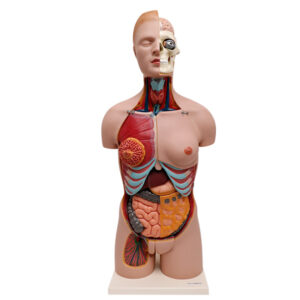

Tamanho natural do modelo de torso humano

Modelo de torso humano